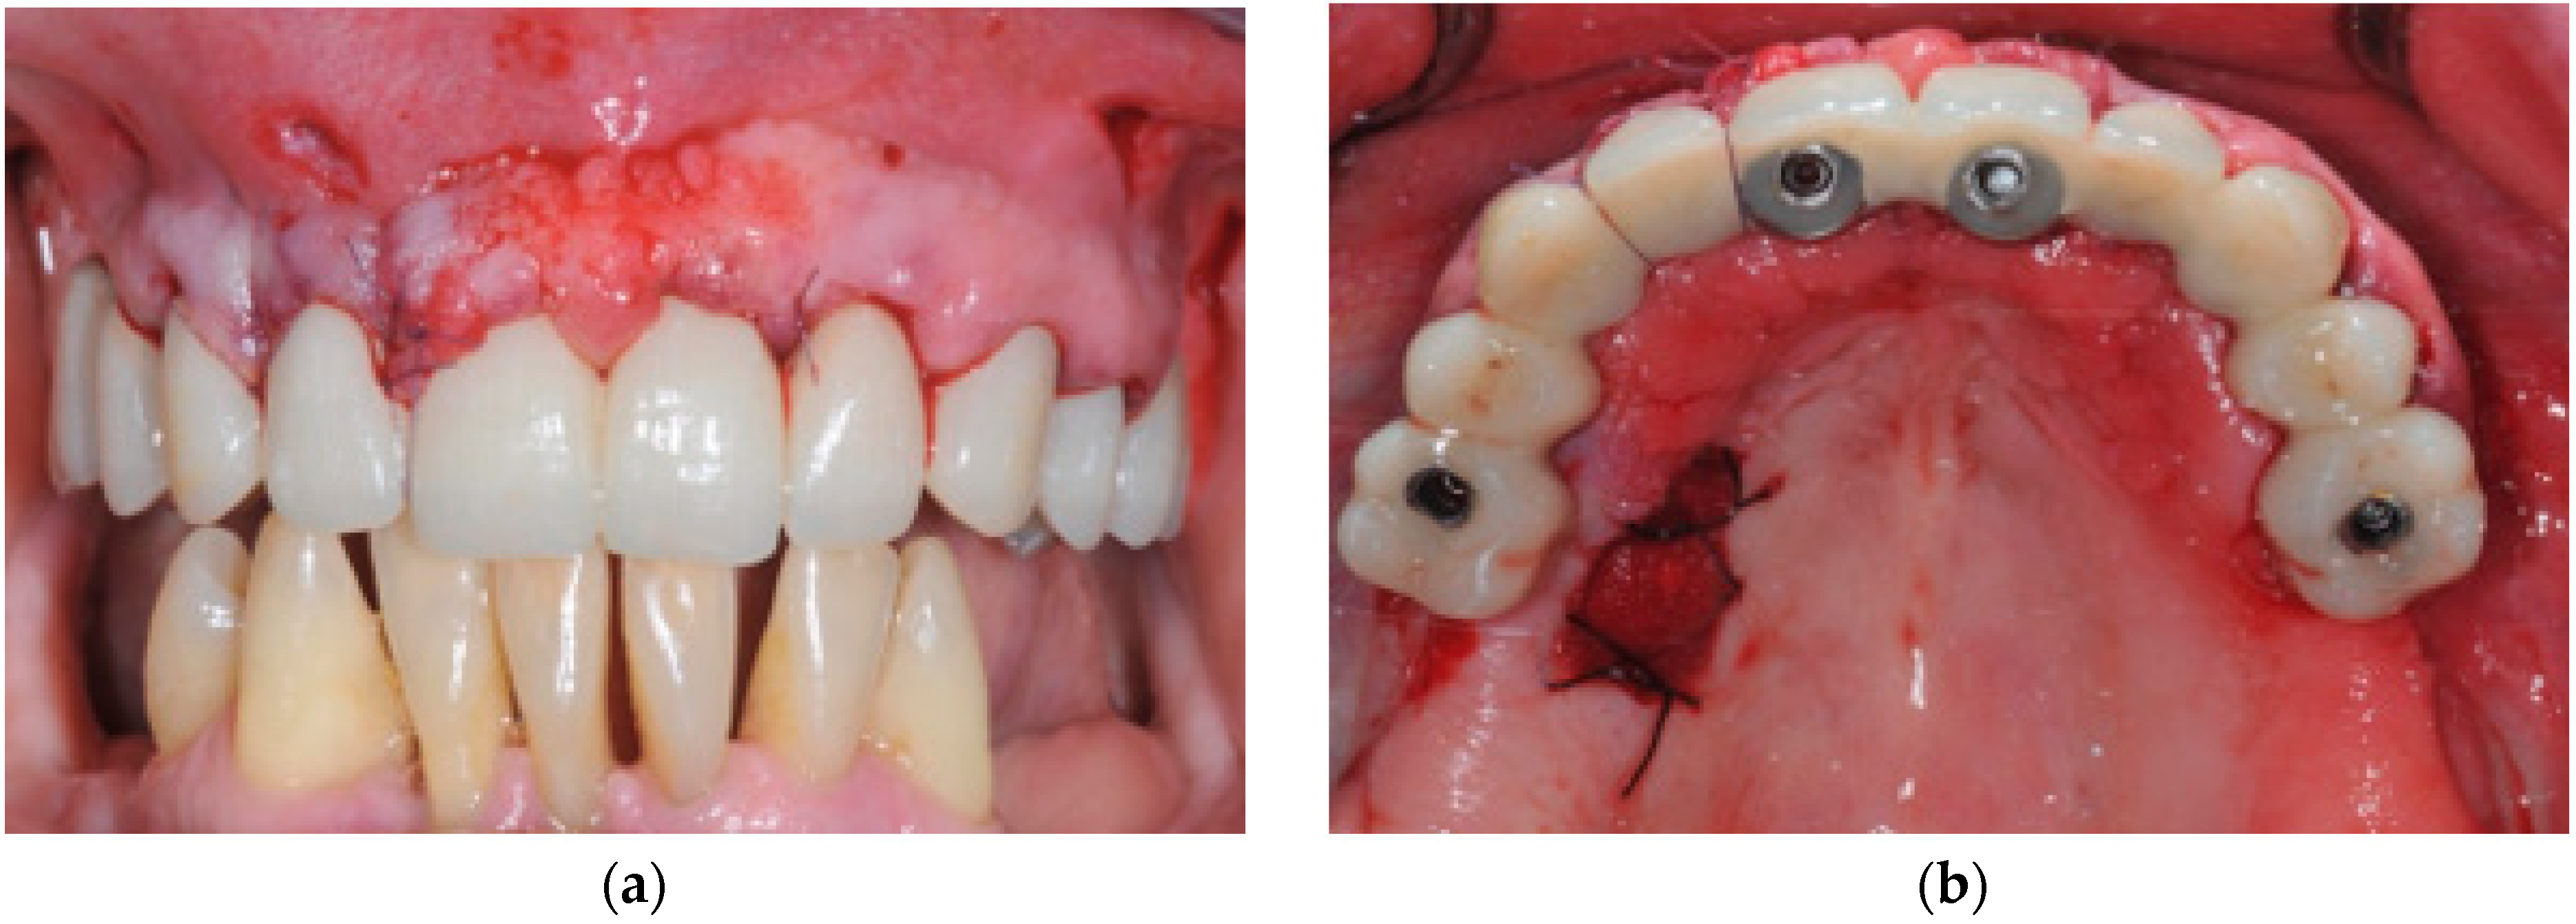

2. Materials and Methods